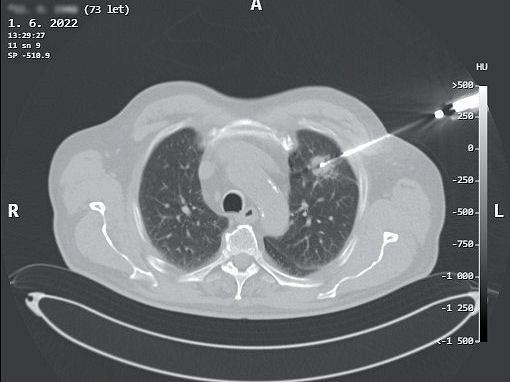

uzlinách. Indikující chirurg je však často v situaci, kdy se primární ložisko v plíci podezřelé z maligního původu nezdařilo verifikovat bronchoskopií s biopsií nebo kar táčkovou cytologií, ani punkční transparietální biopsií pod CT (obr. 3.9, 3.10).

Opakovat tato invazivní vyšetření a znovu čekat na výsledky donekonečna nelze. Známé nebo neznámé histologické zařazení nádoru a jeho typ sám o sobě ne jsou indikací nebo kontraindikací videotorakoskopické ho výkonu. Rozhodující pro indikaci videotorakosko pické operace je videoskopická dostupnost patologické afekce k spolehlivé a bezpečné peroperační bioptizaci a peroperačnímu histologickému určení, pokud je nutné – jak bylo zmíněno v předchozím textu.

obr. 3.10 Transparietální biopsie plic je vedle bronchoskopie metodou volby u intervenční diagnostiky plicních nádorových afekcí (a, b). Výtěžnost rovněž nemusí být stoprocentní. Navíc tzv. negativní výsledek histologického vyšetření bioptického vzorku ještě nedává jistotu vyloučení malignity